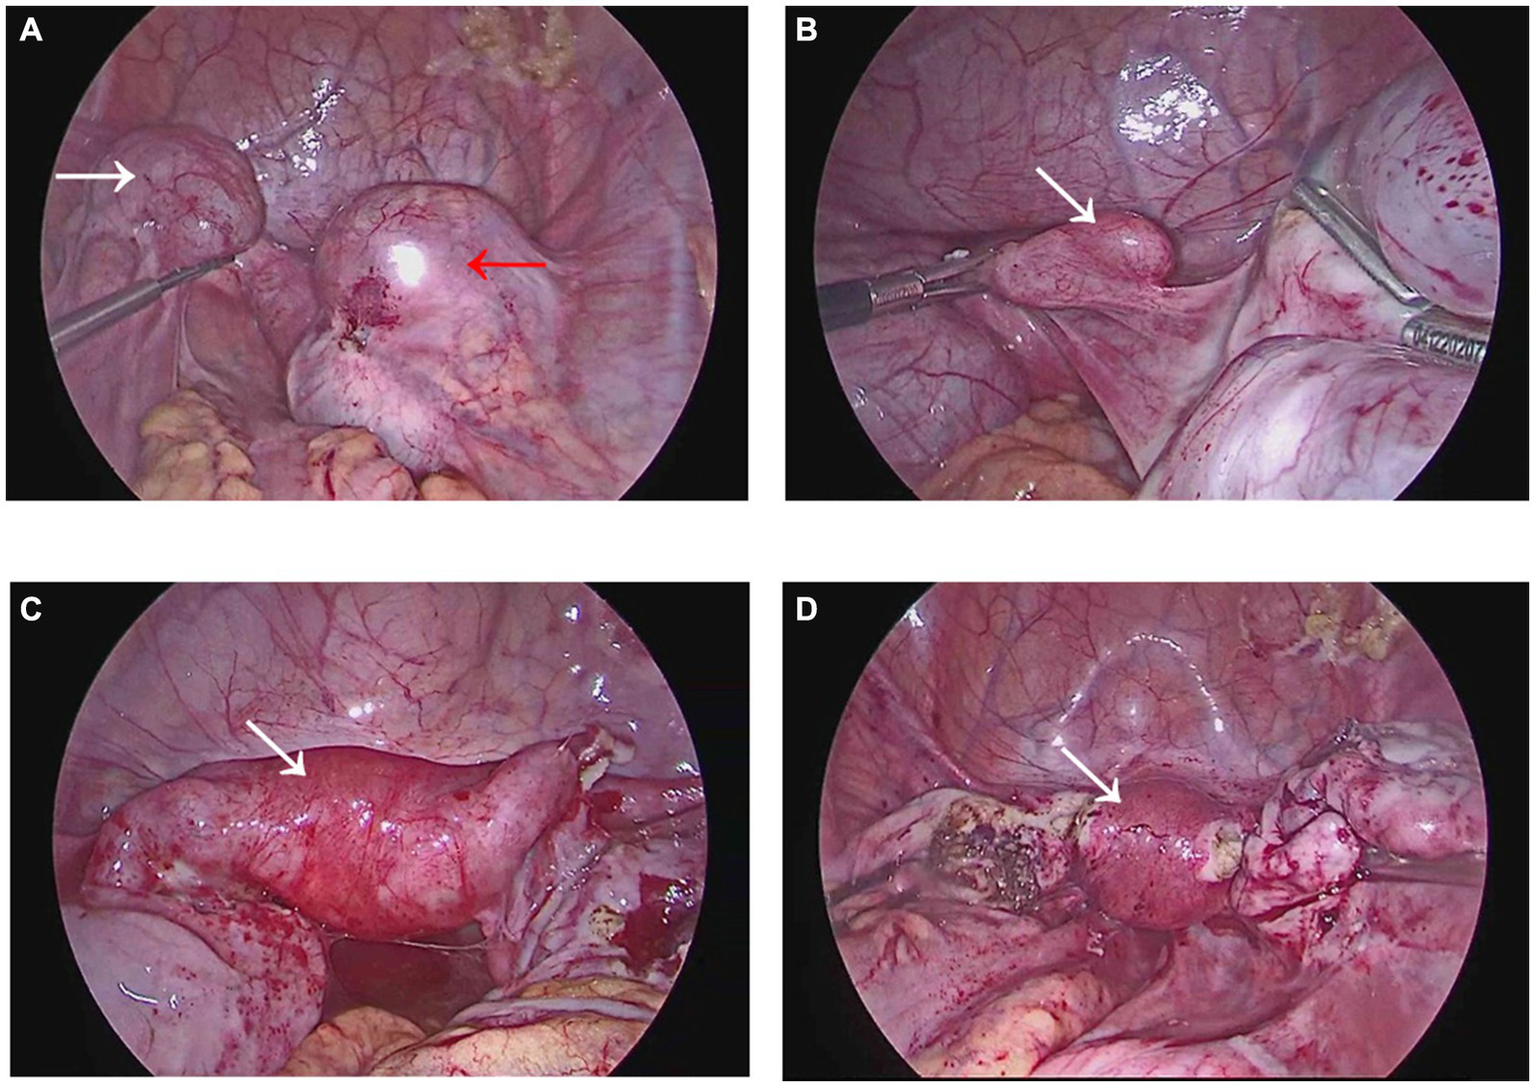

During the surgical intervention, hysteroscopy (ShenDa J0100A, China) revealed a single cervix with normal cervical canal morphology. The length of the cervical canal was 4 cm, and a transverse septum was identified 7 mm above the internal opening of the cervix, preventing access to the uterine cavity Figure 2A. The septum was punctured using an transabdominal US-guided (Mindray M11T, China) probing needle, unveiling the presence of brown menstrual blood, as illustrated in Figure 2B. An oblique adhesive band was observed extending from the right side wall of the uterine cavity to the septum, and the opening of the right fallopian tube was visible, as displayed in Figures 3A,B. While the adhesive band was separated to expose the right uterine cavity, the opening of the left fallopian tube was not visible. Ultrasound showed that the left and right uterine cavities remained unconnected, and an oblique septum was found from the bottom of the left uterine wall to the left lateral wall. Miniature scissor was employed to excise the weaker portion of the septum, gradually exposing the left uterine cavity. No menstrual blood retention was found inside, and the opening of the left fallopian tube was visible (Figure 3C). Most of the endometrium was defective, with only a small amount of endometrial tissue noted at the bilateral uterine horns (Figure 3D). The two-dimensional model of the uterine cavity is portrayed in Figure 4. During laparoscopic examination, the left interstitial of the fallopian tube was thick and twisted, and a tubular structure over 3 cm long was observed at its proximal end, whereas no lumen or umbrellum structure was observed at the distal end. Besides, the left fallopian tube and left ovary were wrapped and adherent to form a mass of about 4*3 cm (Figure 5A). At the same time, the right ovary was cystically enlarged by approximately 5*5*4 cm, exhibiting a multilocular morphology and filled with clear fluid (Figure 5A). A blind end of approximately 3.5 cm long was noted in the right fallopian tube, and no umbrella structure was observed (Figure 5B). The uterus was flat in the posterior position and measured about 4*3*3 cm (Figure 5C). Following the separation of pelvic adhesion, hysteroscopic intubation was performed on the fallopian tube. The left interstitial area was blue-stained, with no methylene blue outflow observed at the distal end of the left fallopian tube. Consider that bilateral fallopian tubes may be non-functional, bilateral fallopian tubes were excised after communicating with the patient’s family. While the cystic area of the right ovary was physiological. The external outline of the uterus after hysteroscopic metroplasty reveals a fullness at the base of the uterus, indicating that uterine morphology was restored (Figure 5D). Prior to terminating the procedure, an intrauterine balloon was placed, and 4 mL of normal saline was injected. The intrauterine balloon was retained for 5 days post-operatively, and one cycle of Femoston (2 mg:10 mg) was administered to the patient.

Figure 5

Images during laparoscopy. (A) The white arrow points toward the adhesion in the left attachment area, while the red arrow points toward the adhesion in the right attachment area. (B) Displays the blind end of the right fallopian tube. (C) Exhibits the external uterine silhouette prior to hysteroscopic metroplasty, with a slight downward depression near the base of the left uterus. (D) The external outline of the uterus after hysteroscopic metroplasty reveals a fullness at the base of the uterus, indicating that uterine morphology was restored.